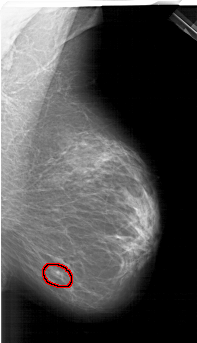

FILE: A_1299_1.RIGHT_MLO.OVERLAY

TOTAL_ABNORMALITIES 1

ABNORMALITY 1

LESION_TYPE MASS SHAPE OVAL MARGINS CIRCUMSCRIBED

ASSESSMENT 4

SUBTLETY 3

PATHOLOGY BENIGN

TOTAL_OUTLINES 1

BOUNDARY